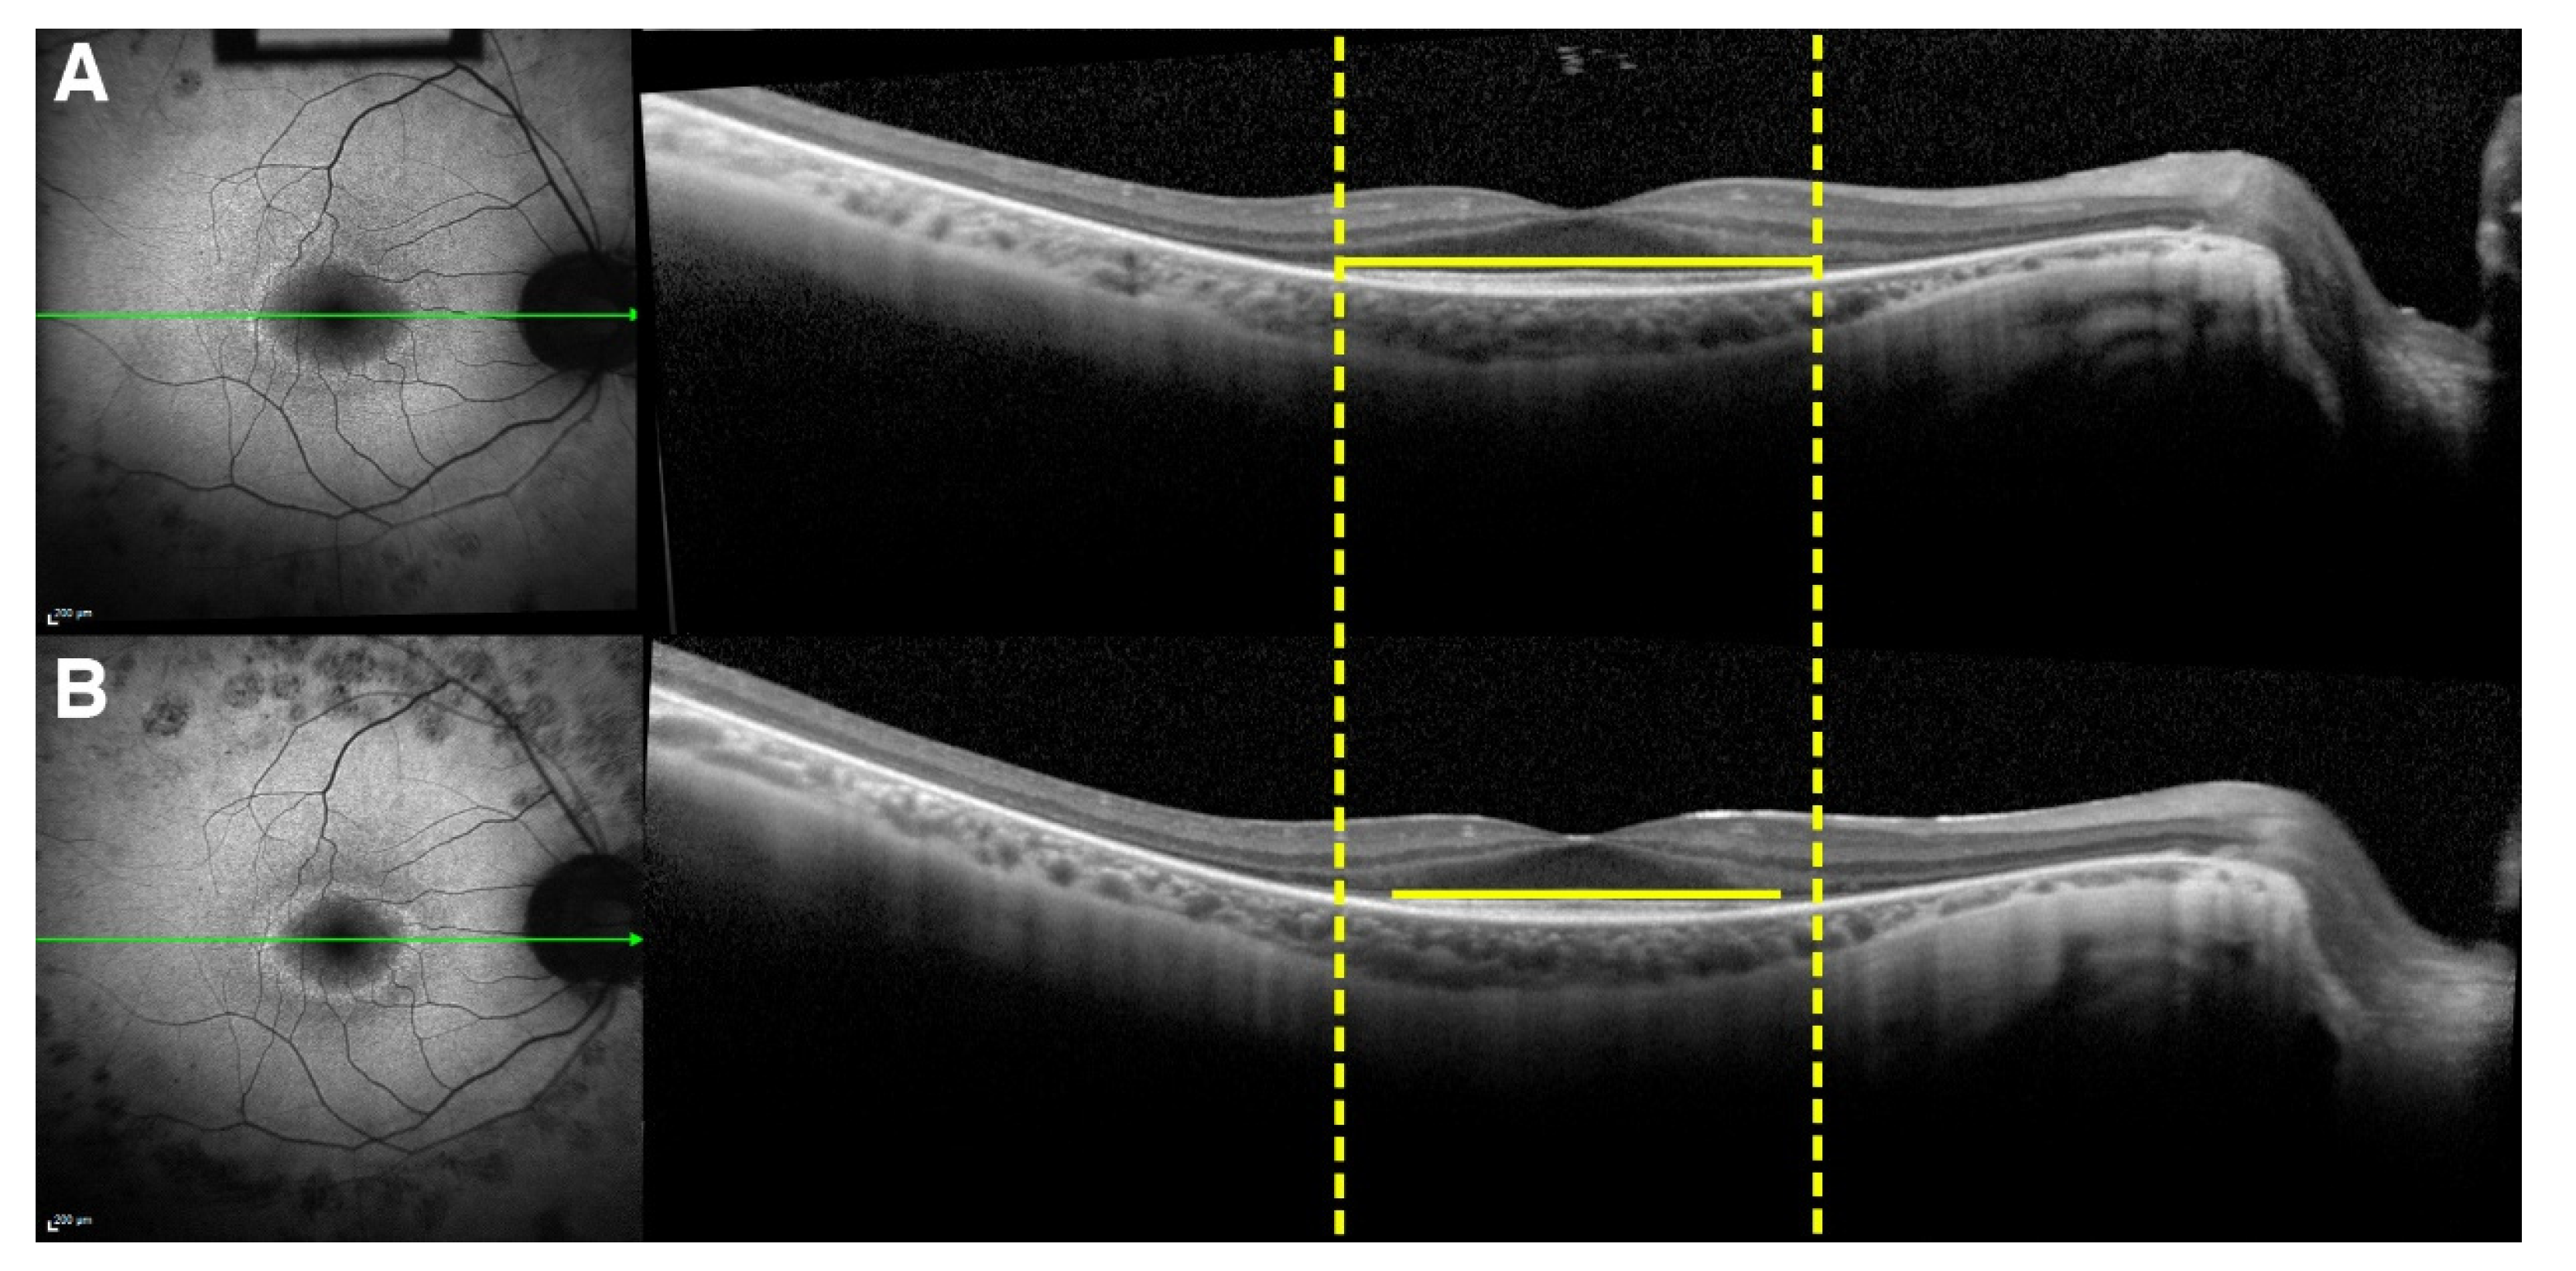

The external boundary of the hyperautofluorescent ring was manually measured by its horizontal and vertical diameters using the measuring tool provided in the Spectralis software (Figure 6). In cases in which a complete ring was not seen, only the observable axis was measured. The external edge of the ring was preferred over the internal edge owing to its greater definition and distinct appearance, allowing for more precise measurements. The interest in studying photoreceptor survival led to the decision to measure the EZ line width due its reliability, as opposed to the interdigitation zone (IZ) line, which cannot always be distinguished, even in normal subjects [30]; the EZ line is readily detectable in every patient. The EZ width was manually measured on the high-resolution horizontal scan through the fovea using the measuring tool in the Spectralis software (Figure 7).

Ellipsoid zone (EZ) line progression in spectral domain–optical coherence tomography (SD-OCT) imaging of a patient with retinitis pigmentosa (RP). Green lines represent the position of the horizontal OCT scan with respect to the autofluorescence image. Dashed yellow lines are tangential to the lateral ends of the EZ line shown in the horizontal SD-OCT cross-section through the fovea at the baseline visit (A). The EZ line width, indicated by the span of the yellow lines, is greater at the baseline visit than at follow-up (B).

Figure 7.